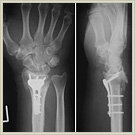

橈骨遠位端骨折:

転倒などにより手を着いた時に生じる頻度の高い手関節の骨折です。閉経後女性に多いですが、若い人でも強い外力が加わると骨折します。手術は、プレートと螺子を用いて骨をできるだけしっかりと固定します(ロッキングプレート)。当院では骨折の形態によってプレートを掌側もしくは背側に使い分けて設置しており良好な成績を得ています。